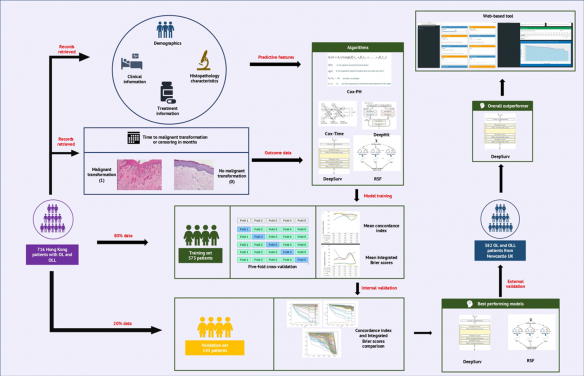

來自香港大學(港大)牙醫學院、李嘉誠醫學院,瑪麗醫院病理部,以及昆士蘭詹姆士庫克大學醫學與牙科學院的研究人員,共同研發了一個網上平台,在輸入相關資料後,能針對患有OL或OLM的病人,預測他們的口腔癌病變風險,預測期長達20年之久。網上平台開放給醫護人員和公衆免費使用。

研究團隊採用「DeepSurv」人工智能演算法,此演算法預測癌症病變的表現優異,經一連串的驗證練習後,能根據病人的一般個人統計資料、臨床和病理數據,以及治療資料等準確預測病人罹患的風險。他們利用香港和英國紐卡素泰恩的OL和OLM的病人數據,訓練人工智能平台並測試其準確度。由於這些病人已被跟進多年,其病歷發展已經明朗,可與平台的預測對照。測試證實,新平台能準確推算這些病人的實際病變發展,在他們每個復診的時間點,平台預測的癌症風險水平與實際情況相吻合。

在香港用作驗證的716名病人的數據,「DeepSurv」能正確預測95% 病人的癌症風險水平。在反映預測準確度的Brier綜合得分是0.04。通常預測工具如果得分低於0.25,已可轉化作實際臨床應用。

而利用英國紐卡素泰恩的382名病人數據,平台正確預測82%病人的風險水平,表明其對不同的人口也具實用性。

團隊期望這人工智能工具有助改善口腔癌的預防和早期診斷。利用開放平台,醫護人員可為高危患者制訂監測時間表和治療策略,對資源有限的醫院,有助其確定處理病患的優先次序。

使用平台預測病變風險,需輸入二十六項有關病人的個人背景資料、病症的臨床和病理描述,以及接受的治療等。就每個個案的風險評估,平台會呈現一條曲線,展示每個時間點預測的風險級別。而當患者達到一定的風險水平時,醫護人員可開始加密對患者的監察。(圖一)